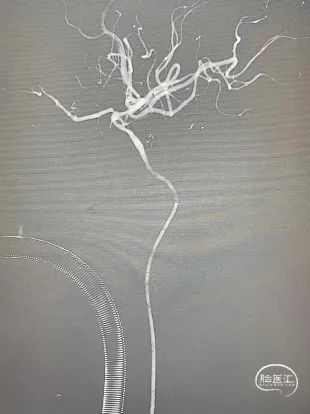

术中脑血管造影:

随后串联病变越过起始部。